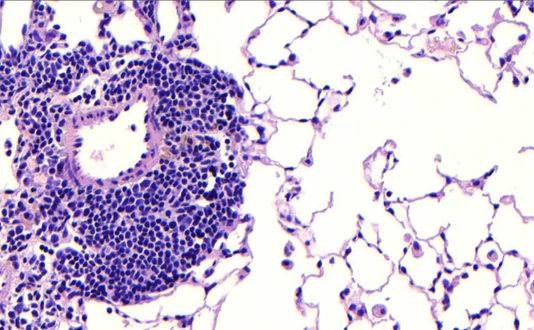

Histology of human cells

AI, New Research Findings, Computational Health, ICB,

New Foundation Model Reveals How Cells Are Organized in Tissues

Researchers at Helmholtz Munich and the Technical University of Munich (TUM) have developed Nicheformer, the first large-scale foundation model that integrates single-cell analysis with spatial transcriptomics. Trained on more than 110 million cells,…